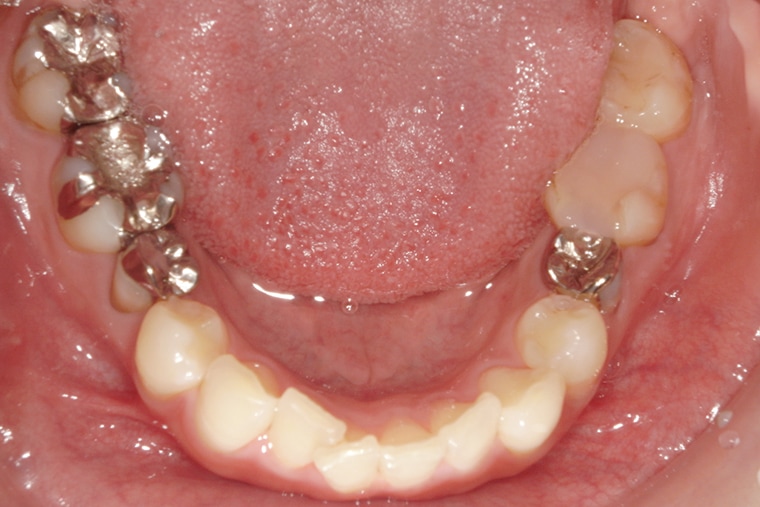

Case Study32歳女性ガタガタな歯のマウスピース矯正-矯正期間6ヶ月(2024年1月開始)